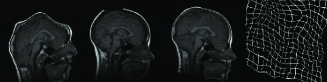

Another method to evaluate proposed registration method is visual examination of checkerboard images. Figure 10 shows an elastic registration example together with checkerboard image illustrating how well the image pair is registered. Checkerboard image includes white and black squares corresponding to intensity values taken from the registered source and the target image respectively. Our overall observation from experimental results is that multiresolution elastic registration on standard intensity scale can capture both local and global deformations with high accuracy.

Figure 10: First row includes the source and target images, second row shows registered source with warped grid and checkerboard image for visual assesment

Refer to caption